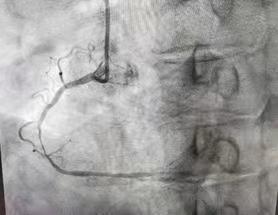

来自渭南市临渭区的患者杨某是首位获益者。患者杨某,80岁,以“胸部憋闷不适一周余”来渭南市第一医院心脏中心就诊,经心电图及抽血等检查后,显示为“急性下壁心肌梗死”,行造影检查结果显示:前降至与对角支分叉处及中段血管狭窄严重,右冠近中段严重狭窄。

图为患者三支血管病变,保守治疗风险较高,要分次手术,与家属充分沟通后行支架植入手术

在唐都医院张东伟教授团队充分的术前准备、精准操作下,在科室负责人梁兴盛医师、谢军芳副主任医师、王伟副主任医师介入团队的共同协作下,使用“crush”双支架技术,成功为患者实施了前降支与对角支分叉处支架植入手术,术后造影结果显示,患者堵塞的血管血流通畅,患者胸痛症状缓解。